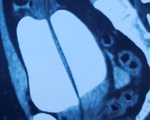

Đoạn dây tai nghe trong bàng quang của người bệnh trên phim chụp X-quang - Ảnh: Bệnh viện cung cấp

Trước đó, bệnh nhân 25 tuổi nhập viện với triệu chứng tiểu khó, tiểu buốt, tiểu rắt. Qua thăm khám, dựa trên phim chụp X-quang, các bác sĩ phát hiện một đoạn dây tai nghe dài chừng 20cm trong bàng quang của nam thanh niên.

Theo ThS.BS Nguyễn Như Trung - khoa ngoại thận tiết niệu, đoạn dây tai nghe điện thoại nằm cuộn tại bàng quang của người bệnh. Tiến hành lấy bỏ dị vật ra ngoài, bác sĩ nhận thấy niêm mạc bàng quang, niệu đạo có hiện tượng viêm đỏ.